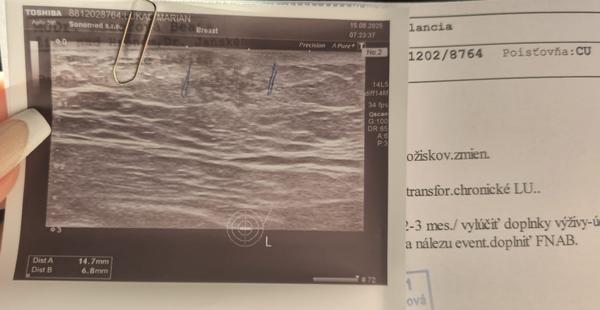

Gynekomastia - to ma najpravdepodobnejsie z anabolik.

Vyzera to na tukove ale ssma vidis ze to chcu sledovat kedze KO uz o 3m.